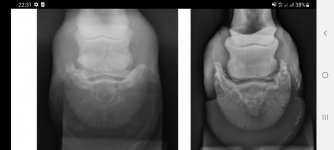

Конь перманентно показывает то хромоту то спотыкание на одну и ту же ногу. Я бы рентгенила одну ногу. На предмет артроза, чипов или старой травмы.

Ясное дело, что вотпрямщас рентген половины лошади я всё равно не потяну, так что пока планирую хотя бы эту одну ногу. Но если артроз или чип, то логично и соседнюю снимать на всякий случай.

Раньше считалось, что спотыкания указывает на заболевания челночного блока. Овердохрена денег не надо. Можно самостоятельно тесты провести.

Каждый сустав сгибается по своему. Когда проверка на навикулит, то там ставится копыто на дощечку и эту дощечку плааавнооо поднимают. Но итог всегда один: пробежать по тведрому.

Навикулит бывает, если оставили длинный зацеп при расчистке, "сломали копытную ось". И тогда хромота всё усиливается и усиливается с каждым днём. Нет, это даже не хромота, а спотыкание - ступает не с пятки, а с зацепа и цепляет зацепом за грунт.

К счастью, если уж придётся его вызывать, то будет рентген в любом случае, и можно будет легко увидеть угол копытной кости по отношению к земле. Если расчистка действительно кривая, то тогда исправлю, разумеется. Вообще длинных зацепов не имею привычки оставлять, копыта сами по себе быстро отрастают, даже раз в месяц расчищать - уже много. Отросшая стенка расплющивается под весом и начинает торчать в бок. Это ещё худо-бедно можно отнести к длинному зацепу, но на поле конь споткнулся с условно свежеподпиленными копытами (неделя). И вот сейчас уже опять пора, лишнее само обкалывается криво на камушках.

Вряд ли навикулит, но ни один вариант я полностью не вычёркиваю.